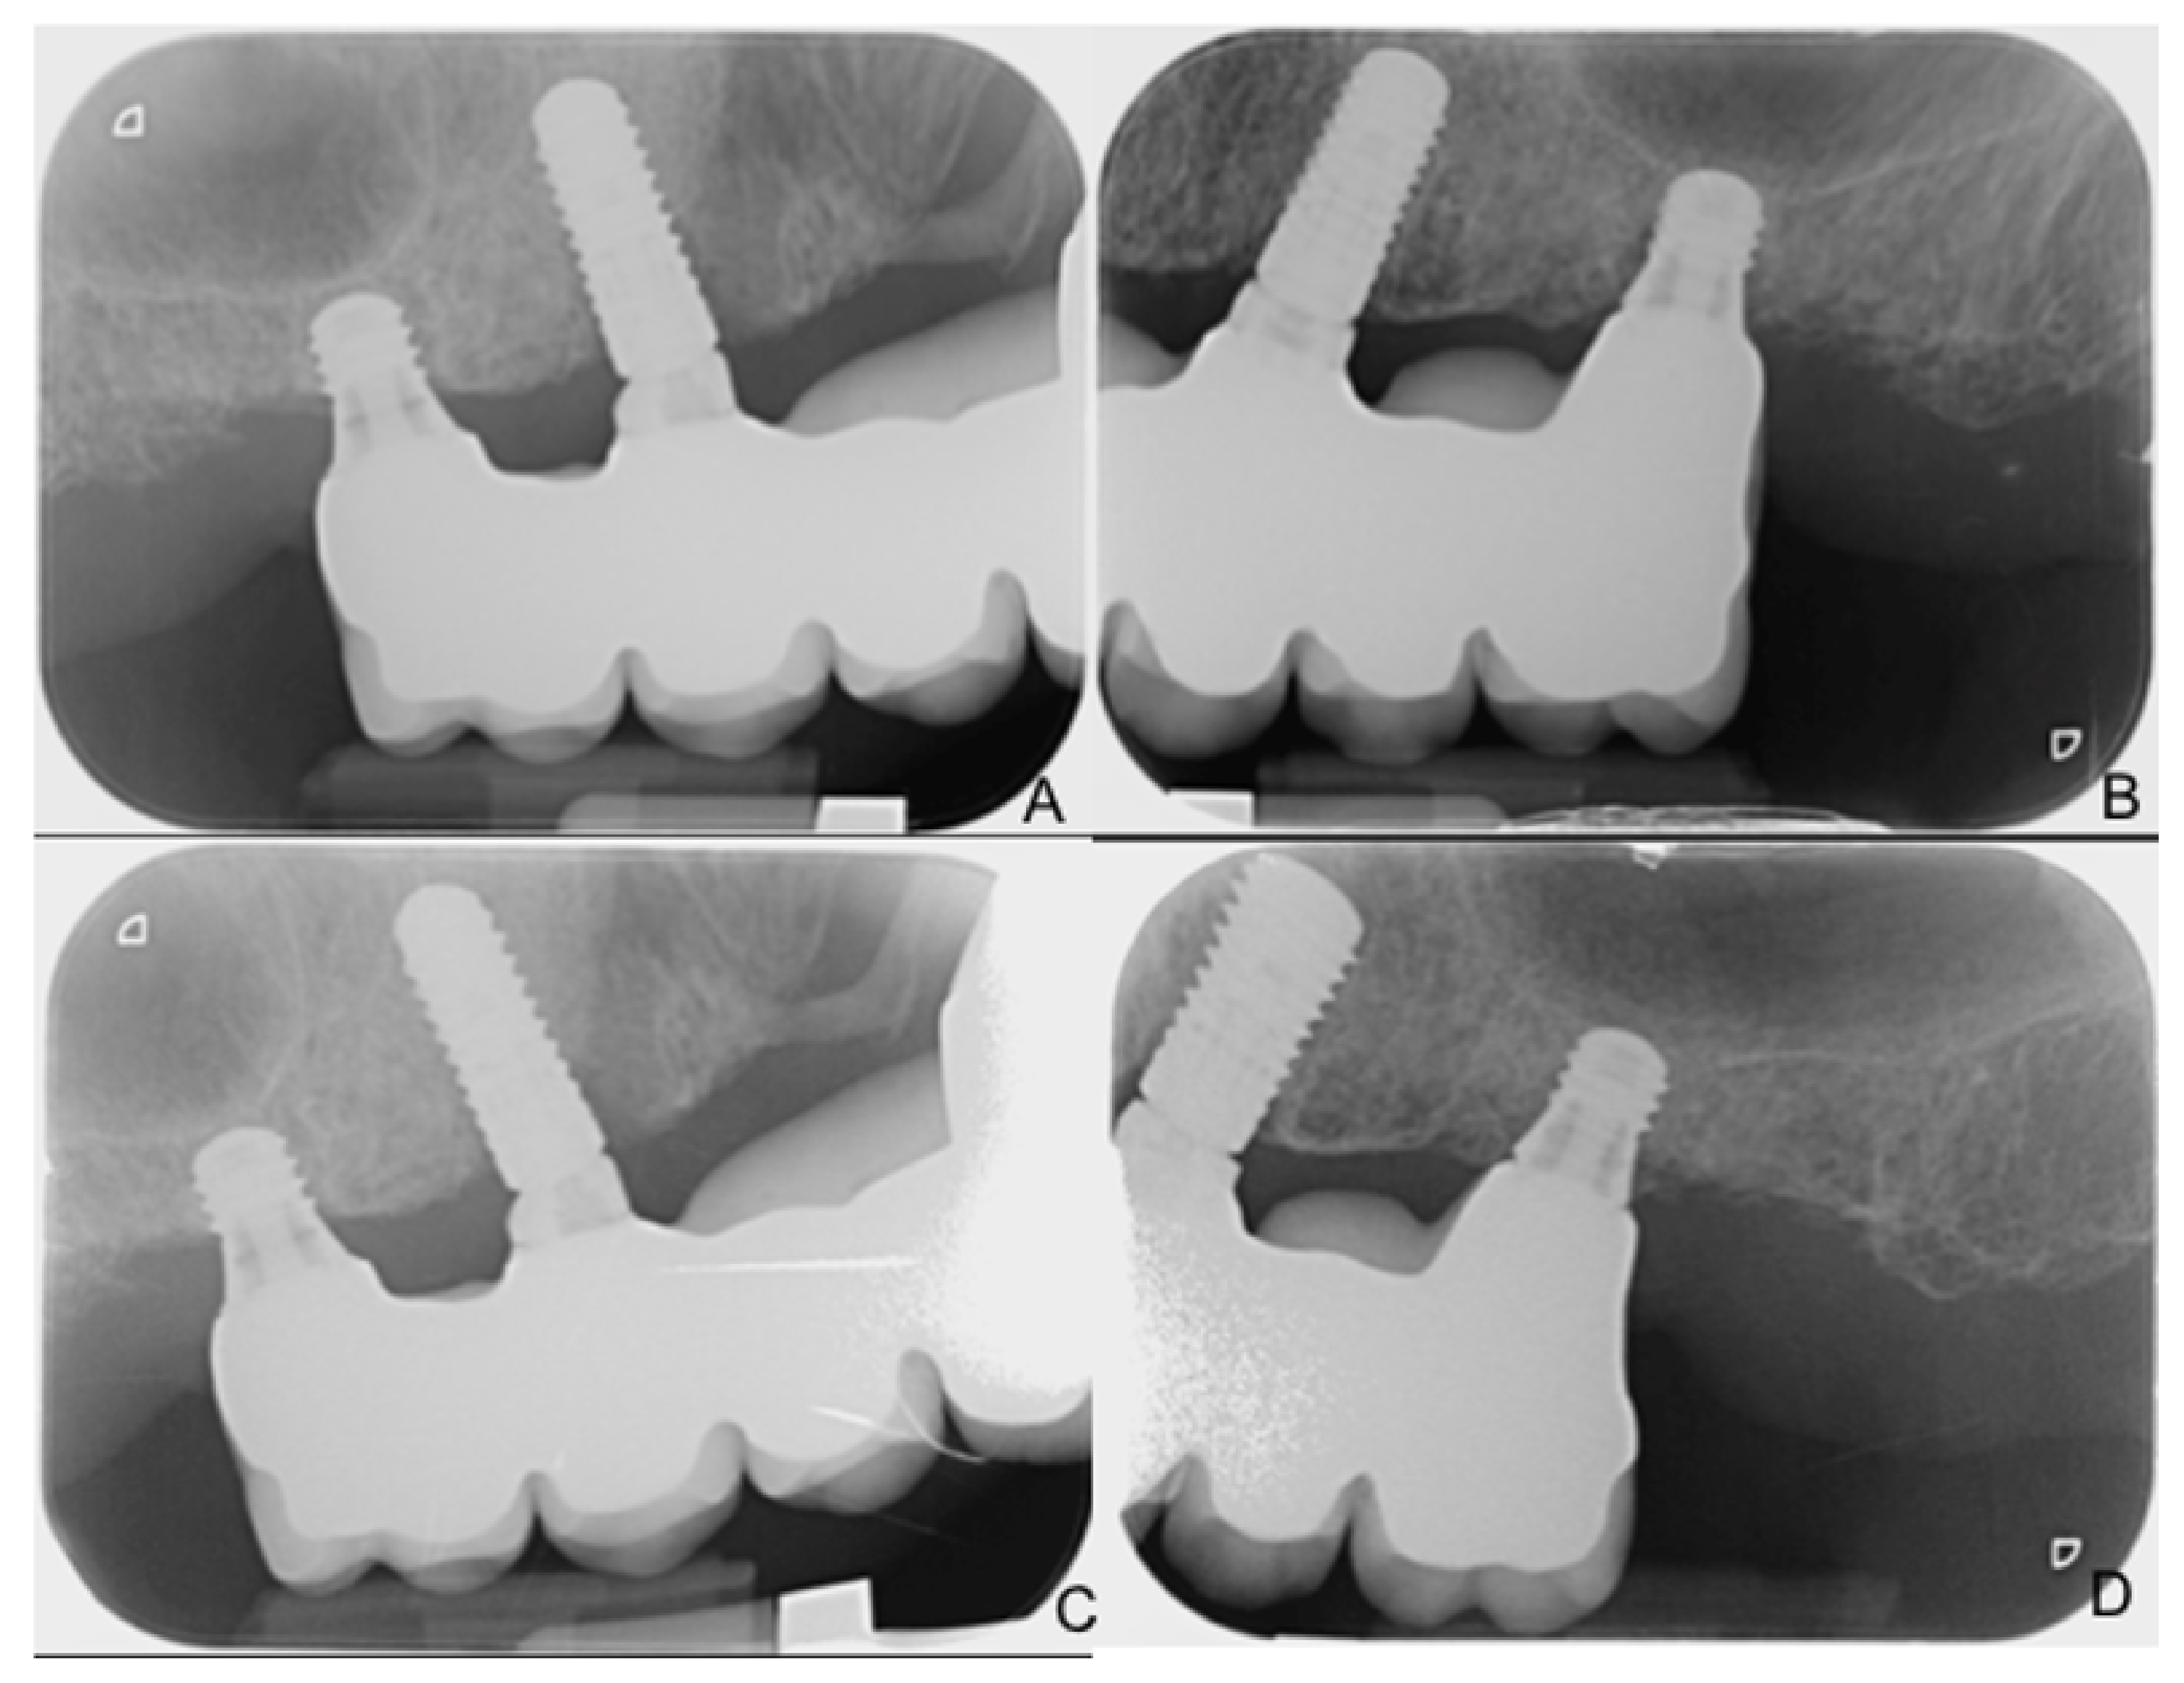

Two-Year Follow-Up of 4-mm-Long Implants Used as Distal Support of Full-Arch FDPs Compared to 10-mm Implants Installed after Sinus Floor Elevation. A Randomized Clinical Trial

2.11. Radiographic Measurements

| MBL Short | MBL Control | Progressive Changes Short | Progressive Changes Control | |

|---|---|---|---|---|

| Prosthesis delivering (BL) | 0.17 ± 0.41 | 0.28 ± 0.21 | NA | NA |

| 6 months | 0.18 ± 0.34 | 0.49 ± 0.44 | −0.01 ± 0.11 | −0.21 ± 0.33 |

| 12 months | 0.21 ± 0.35 | 0.58 ± 0.44 | −0.04 ± 0.13 | −0.30 ± 0.32 |

| 18 months | 0.34 ± 0.35 | 0.68 ± 0.51 | −0.17 ± 0.29 | −0.40 ± 0.37 |

| 24 months | 0.44 ± 0.37 | 0.84 ± 0.68 | −0.28 ± 0.37 | −0.54 ± 0.49 |